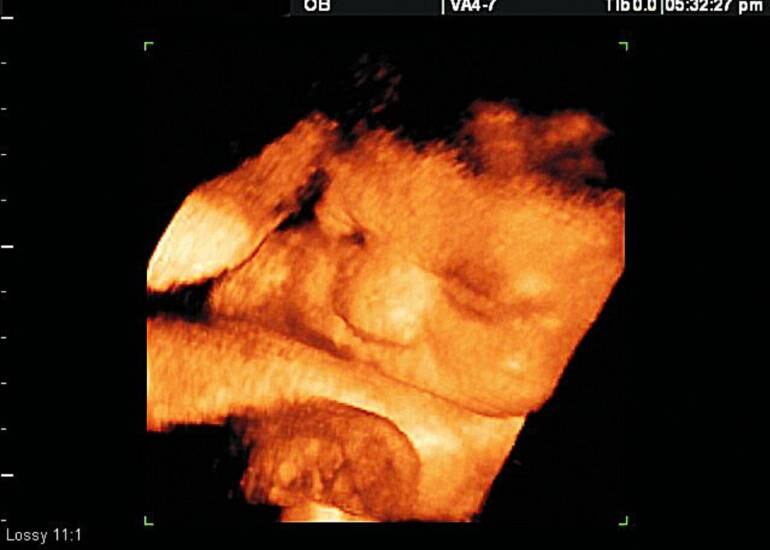

Foto Colprensa